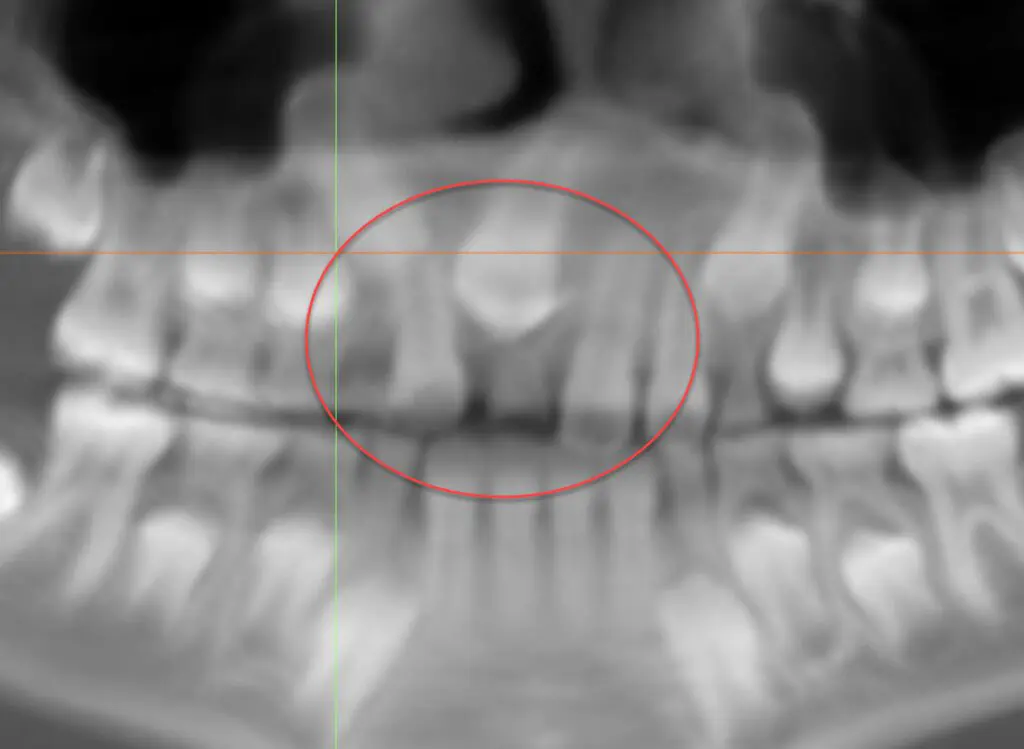

Case 3: Extra teeth. His general dentist referred this patient because his right front tooth wasn’t coming in. The 2D x-ray doesn’t look too out of the ordinary, but in the 3D view, we can see a supernumerary (extra) tooth blocking the eruption of the one we are expecting to see. We were able to refer this patient to an oral surgeon to remove the extra tooth and normalize the eruption pattern.